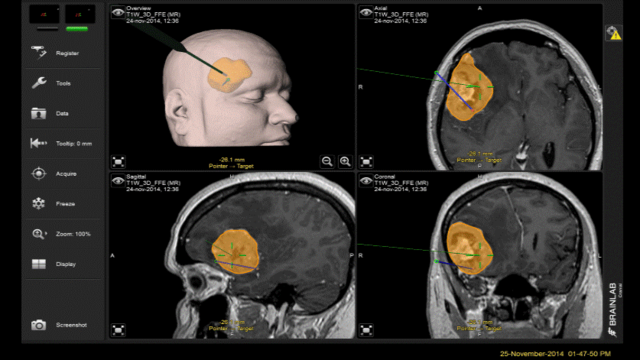

- La cirugía estereotáxica: Es una forma de intervención quirúrgica mínimamente invasiva, que utiliza un sistema de coordenadas tridimensional para localizar pequeños objetivos anatómicos dentro del cerebro mediante un marco colocado en la cabeza del paciente se toman imágenes de diagnóstico (tomografías o resonancias).

Consiste en una sofisticada tecnología informática que tiene como soporte físico un potente computador que incluye un software específico que procesa las imágenes neurorradiológicas digitalizadas.

Es un sistema de planificación prequirúrgica y de guía intraoperatoria sirve como la eliminación de lesiones cerebrales en el interior o adyacente a áreas que tienen riesgo de ser lastimadas las fibras subcorticales que nacen de ellas.